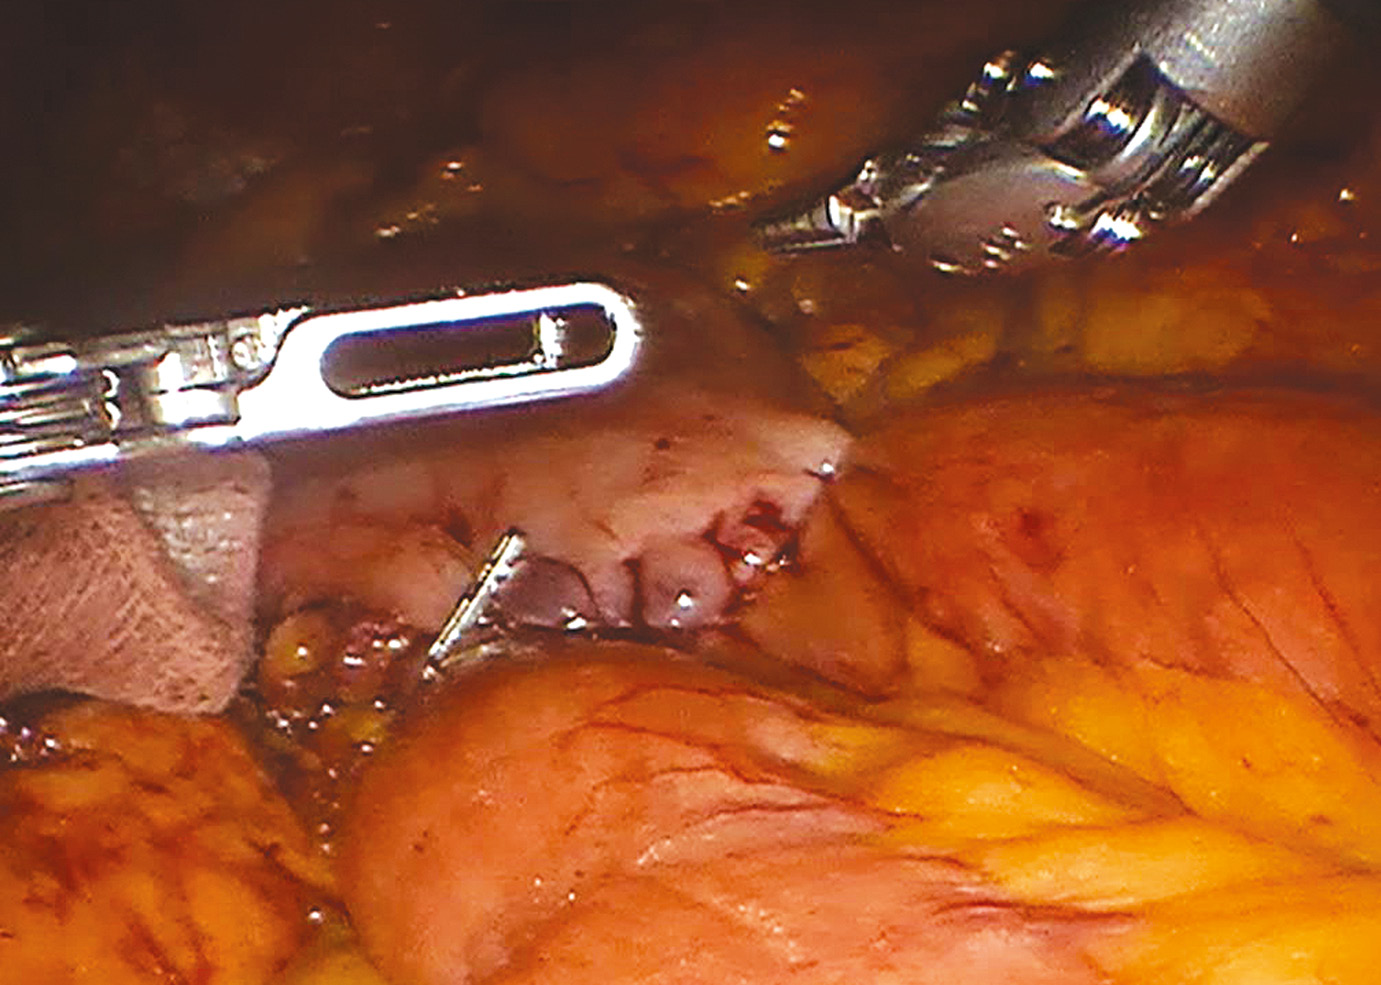

30.09.22 г. выполнено второе оперативное вмешательство – роботассистированная дистальная субтотальная резекция желудка (модификация Бальфура) c лимфаденэктомией D2, формированием интракорпорального гастроэнтероанастомоза и межкишечного анастомоза по Брауну (оперирующий хирург – Р.Н. Комаров).

В условиях комбинированного эндотрахеального наркоза осуществлён доступ в брюшную полость по Хассону, троакары установлены стандартно, в условиях карбоксиперитонеума проведена ревизия органов брюшной полости, данных за наличие отдалённых и регионарных метастазов не получено. Визуально опухолевое образование не определяется. Осуществлён докинг роботической консоли DaVinci Si (Intuitive, США). Выполнена операция в вышеуказанном объёме (рис. 2, 3). Препарат извлечён через мини-лапаротомию. После установки подпечёночно дренажа выполнено послойное ушивание ран. Пациент гемодинамически стабилен, переведён в отделение реанимации. Время операции составило 225 мин, кровопотеря – около 100 мл.

Рис. 2. Вид опухоли антрального отдела желудка в режиме флуоресцентной визуализации ICG.

Рис. 3. Вид гастроеюноанастомоза «конец-в-бок» однорядным непрерывным швом нитью Stratafix 3-0.